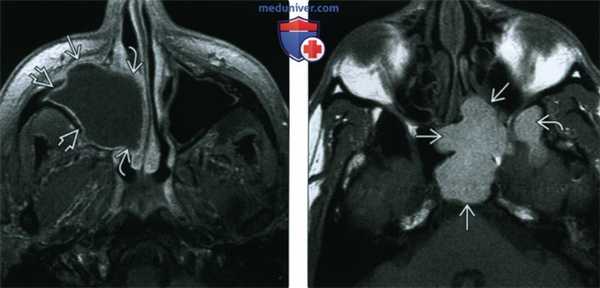

(Слева) При аксиальной МРТ Т1ВИ С+ FS определяется мукоцеле правой верхнечелюстной пазухи с эрозиями передней стенки и распространением кнутри в полость носа. Определяется также периферическое контрастирование слизистой оболочки, но без накопления контраста в центре, что помогает отличить мукоцеле от новообразования.

(Справа) При аксиальной МРТ Т1 визуализируется мукоцеле большого размера в левой основной пазухе, относительно гиперинтенсивное из-за белкового содержимого. Обратите внимание на поражение латерального кармана.

(Слева) На аксиальной МРТ (Т1 ВИ С+ FS) определяется мукоцеле правой верхнечелюстной пазухи с эрозией передней стенки и распроаранением в полость носа. Слизиаая оболочка на периферии накапливает контраст, что помогает отличить мукоцеле от новообразования.

(Справа) На аксиальной МРТ (Т1 ВИ) определяется большое мукоцеле правой сфеноидальной пазухи с однородным гиперинтенсивным сигналом, обусловленным большим содержанием белка. Обратите внимание на вовлечение бокового кармана.